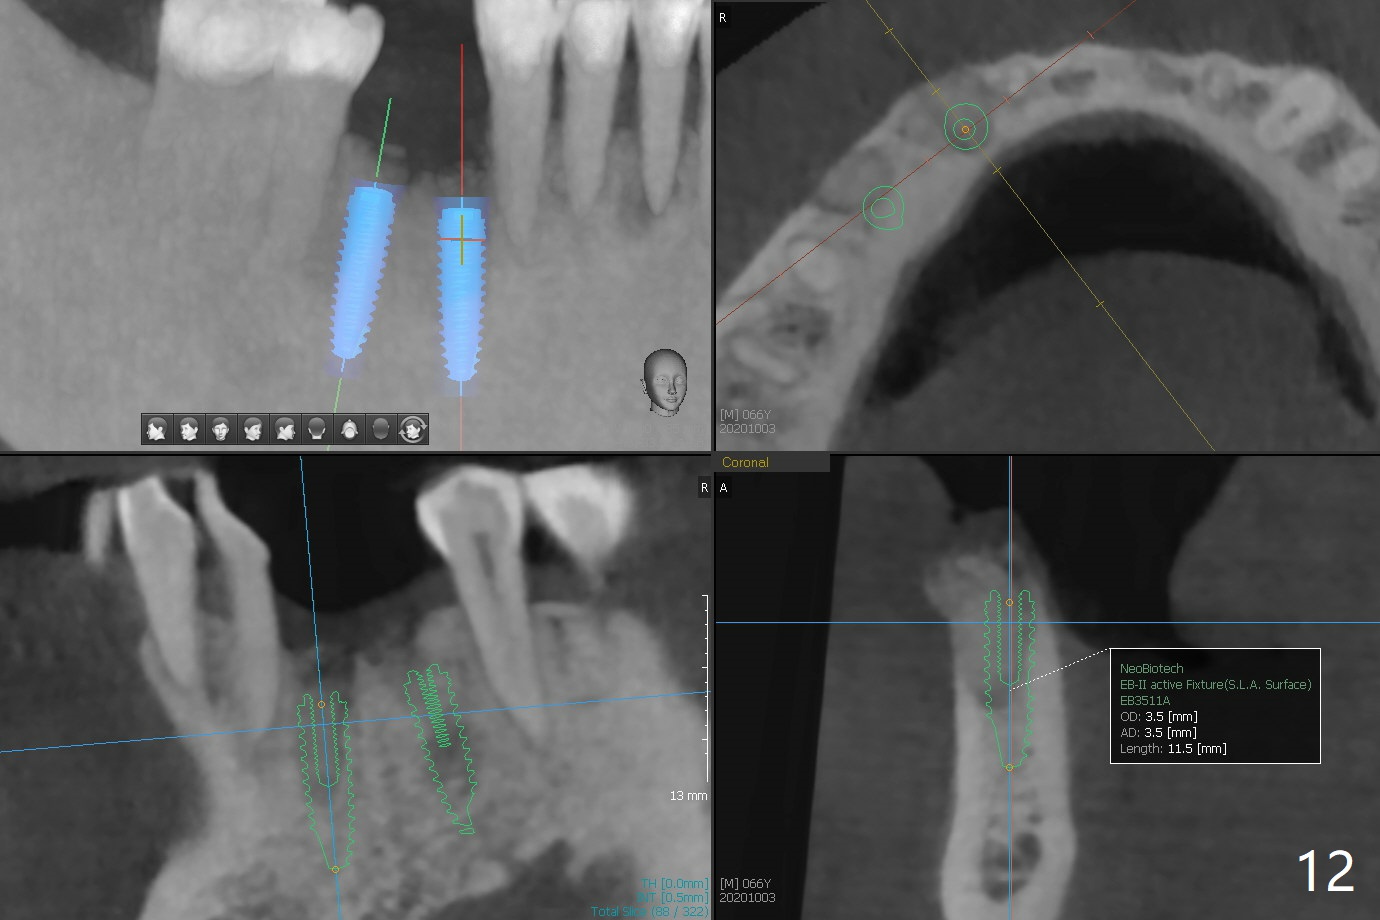

66岁男1.5年前来诊所拍摄全景片(图一),似乎27,28号牙还能保留,今天突然回来,主诉27、28区疼痛瘘道,商量决定先拔除27,28,32及右下深洗。拔除32号牙时发现它接近31区(将要植牙),必须植骨(近中部分(远中塞入胶原塞)),27,28颊侧骨板缺失(大量肉芽组织),植骨理所应当,而且必须拼命推压,但愿推到颊侧骨板,细的皮质骨没有压制感,非要加入粗的松质骨皮质骨,一张12x12毫米胎盘膜剪成两片覆盖27/28和32拔牙窝,4-0 PGA缝线固定,拍摄术后半侧全景片后(图二 (*:骨粉)),使用牙周敷料保护伤口。术后一个月27,28号牙位骨粉保持原位,而且颊侧骨板好像已经重建(图八,十一,九),似乎能植入两个植体(图十,十二)。